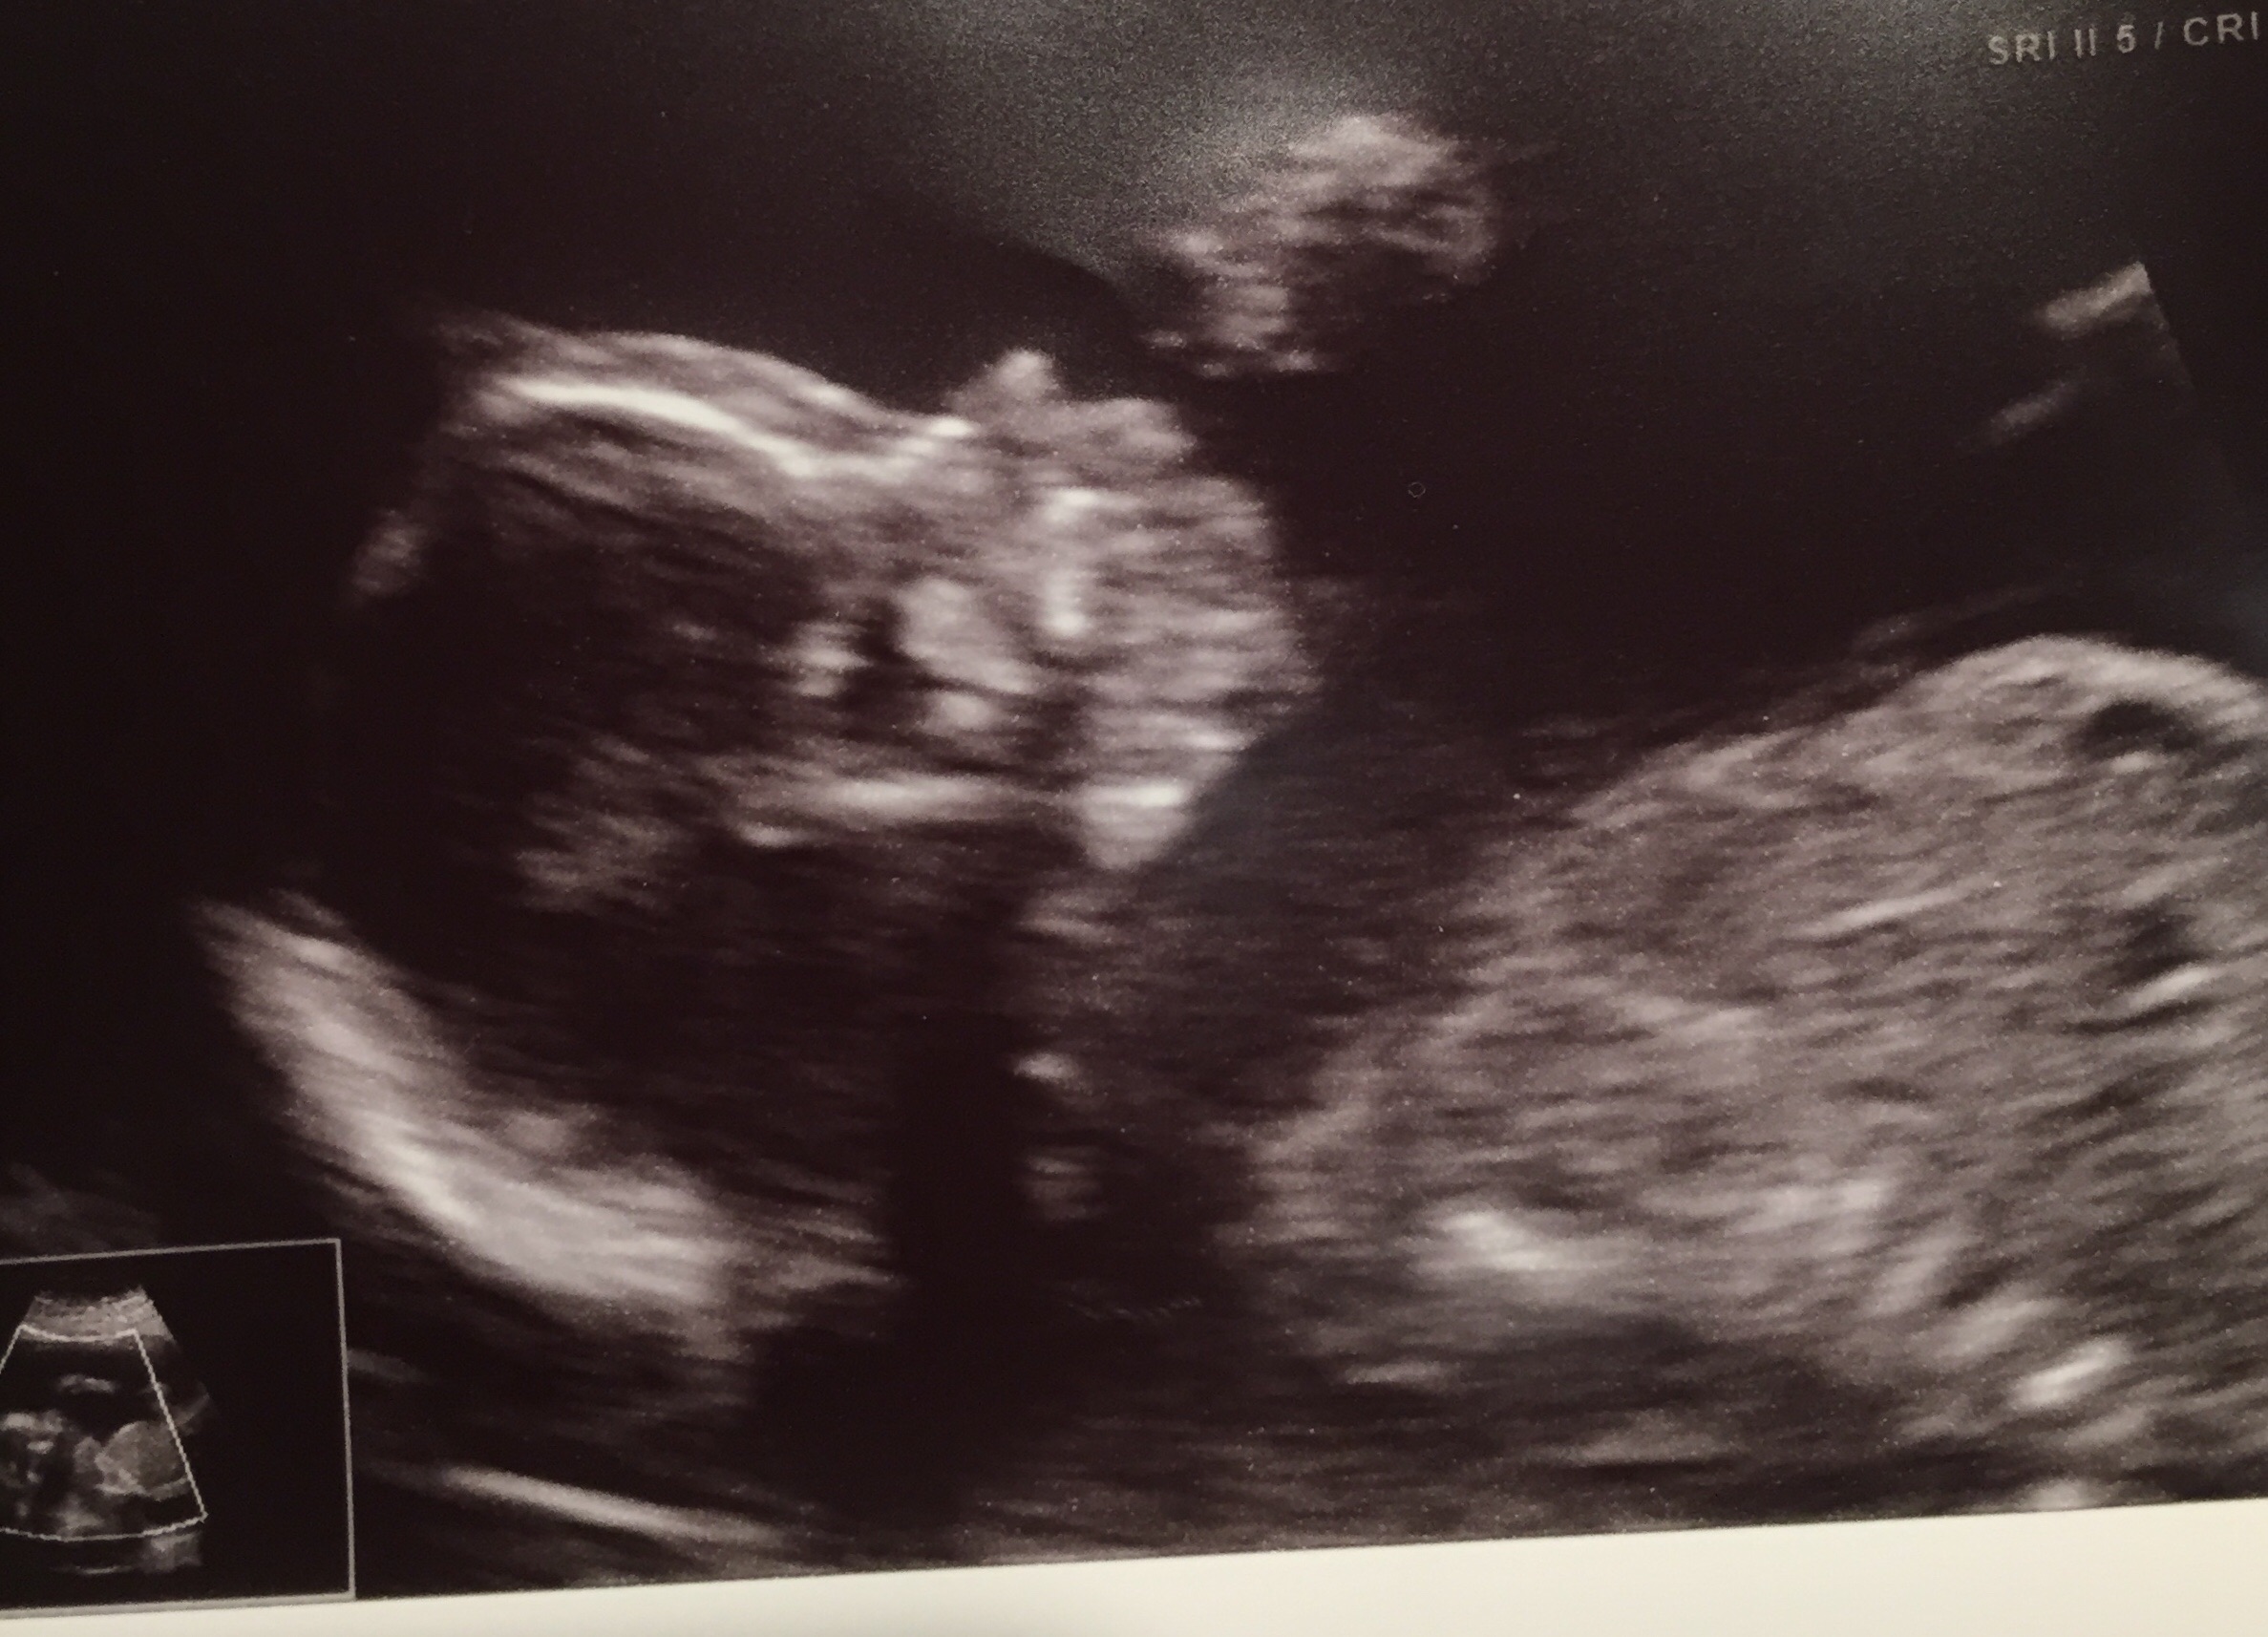

Last Wednesday, I had my a/s appointment. The ultrasound went great, although the ultrasound tech couldn't see the heart and told me I'd have to come back. She said that she got everything else that she needed and that everything looked great. "Great" was her word. Then we were sent to check in with the doctor, and that's when my world just came crashing down. The doctor said that my quad screen had some bad news and the screen had tested positive for down syndrome. I asked what the odds were, and she said 1:20. No explanation, nothing. Luckily, I knew what "positive" meant and knew that this wasn't diagnostic, but it still immediately made my heart drop and sent me and my husband into a panic.

Any support/positive thoughts/positive words/etc. that you can provide would be great. I am at work and have just randomly been bursting into tears. I think the "not knowing" is the hardest part. We are in a weird emotional limbo, and we will be for a couple weeks. I plan on asking if we can take the Harmony test tomorrow, and I know that takes a couple weeks for the results to come back. Thanks ladies. Sorry for not always participating as much as I should. Just know that I am always lurking and reading posts and thinking about all of you and appreciating your presence. UPDATE we had the level II ultrasound and they didn't find any markers or any signs of Down syndrome or other health issues and baby looked so cute!! Geneticist lowered our risk to 1 in 40 which is still scary but not so scary. Had blood test drawn for the Harmony test so just waiting on that now. So much waiting. If any ladies are in the same boat or a similar boat, my thoughts are with you. This has been really hard and I can't wait to know....but we have more hope now.